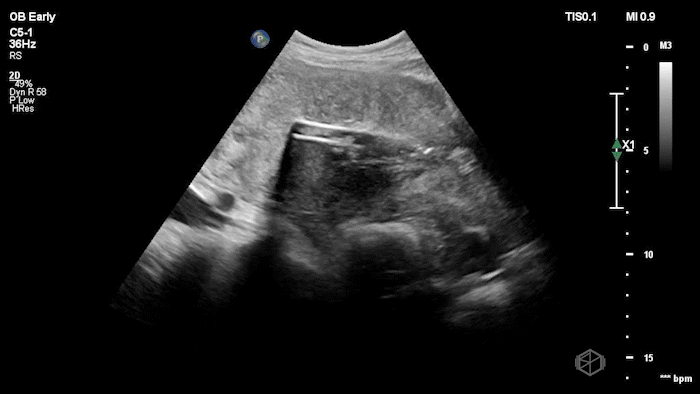

Manual vacuum aspiration - US guided; cooperation between OB and EM!

09A - What procedure is the patient undergoing?

Retained products, large volume of intrauterine heterogenous material consistent with blood clots

09 - What is the diagnosis in this post-partum patient?